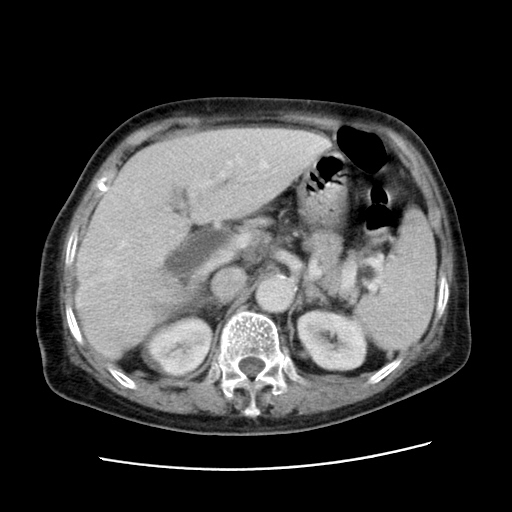

女,77.无不适

肝脏变异、异位胆囊,肝右叶肝内胆管结石并肝内胆管扩张。

肝右叶肝内胆管结石并肝内胆管扩张。

肝右叶肝内胆管结石并肝内胆管扩张

胆总管扩张

肝右叶肝内胆管结石并肝内胆管扩张。胆总管下段梗阻,考虑壶腹部占位。

右侧肝内胆管局限性扩张,其内密度不均匀,扩张的胆管壁增厚,考虑肝内胆管炎合并结石可能性大

肝右叶肝内胆管结石并肝内胆管扩张。胆总管下段梗阻,考虑壶腹部占位。支持